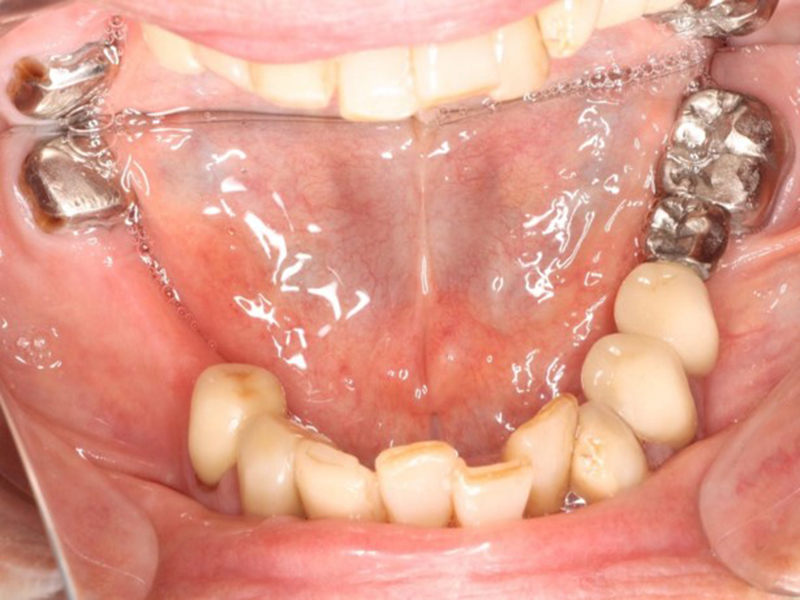

▼ ケース5 下顎前歯部叢生症例

初診時口腔内写真

初診時X線写真